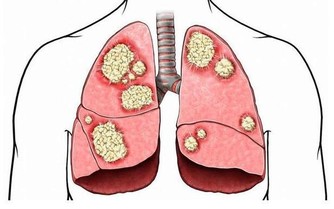

頭是諸陽之會,我們頭部的血管是最豐富,幾乎所有的生理活動都要經頭部神經中樞的命令,它無時無刻都在運作著。一旦頭部的血管有點堵塞了,就會直接影響中樞神經系統,從而引發一系列的心腦血管疾病,對我們的身體健康極不友好。而且頭部的血流量非常大,相當於全身的20%。而且由於腦梗發作而死亡的時間非常快,很少能夠搶救成功,及時搶救過來了,也會留下嚴重的後遺症,對生活帶來極大的影響。

當腦梗出現時,就說明腦部血管出現了堵塞問題,從而表現出異常,影響了對神經的控制,很可能會出現面部神經不受控制的現象,比如面癱、流口水、四肢無力等等。

看東西模糊也是腦梗的一個表現,如果突然發現自己看東西模糊或者看不清楚完整的物體,甚至有的時候還感覺眼前一黑,此時要提高警惕了,由於腦部缺血導致的視網膜功能障礙,嚴重的會影響正常生活,要及時去醫院進行檢查,隨時都有發生腦梗的危險。